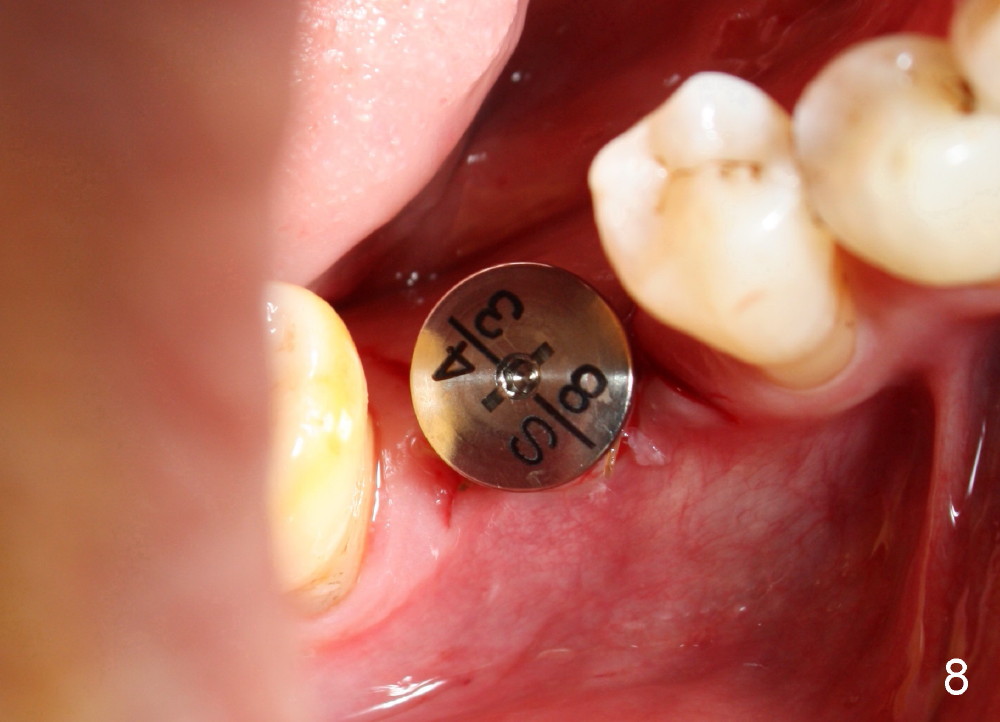

When a positioning pin is placed in the osteotomy with 10 mm deep, the sensor cannot be placed deep enough because of pin interference so no IAC is visible (Fig.4). When the pin is removed and the sensor is placed low enough, IAC is clearly shown, but the osteotomy is barely visible (Fig.5 pink dashed line). With information obtained from pre- (Fig.2,3) and intra- (Fig.4,5) op PA, twelve mm of osteotomy appears to be appropriate. A final implant (5.3x12 mm) is placed with separation from IAC (Fig.6, insertion torque 50 Ncm). A healing abutment is placed (Fig.7,8), which helps retain perio dressing (Fig.9). Two weeks later, the gingiva heals around the abutment (Fig.10). Four months postop, the implant appears to osteointegrate (Fig.11). A cemented abutment is placed (Fig.12). With supragingival margin, oral hygiene is easily maintained (Fig.13). Due to delayed placement, the gingival embrasure is extremely large (*). The issue is much less with immediate implant.